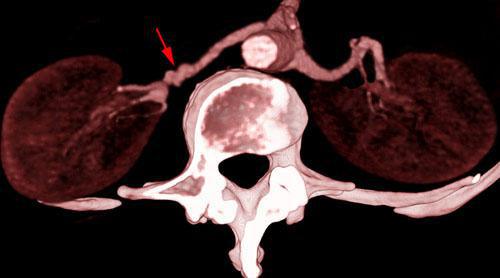

Estenosis intensa de arteria renal 2